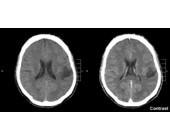

Wie schädlich sind Handy-Strahlen?

Das nationale Forschungsprogramm ist zum Schluss gekommen, dass Handy-Strahlung keinen direkten Einfluss auf unsere Gesundheit hat. Allerdings konnte veränderte Hirnaktivität nachgewiesen werden.